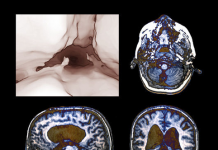

Что такое гидроцефалия

Почему у детей возникает водянка головного мозга. Каковы ее симптомы, диагностика и лечение. Что такое гидроцефалия Гидроцефалия или, как ее еще называют, водянка головного мозга (от...